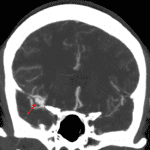

Age: 42

Sex: Female

Indication: Headache

Case #19

Findings

- Large volume acute subarachnoid hemorrhage throughout the right greater than left cerebral hemispheres with the largest concentration of hemorrhage in the right sylvian fissure and suprasellar cistern

- Mild polypoid mucosal thickening of the right maxillary sinus

Diagnosis

- MCA aneurysm rupture

Sample Report

Sample Report

Large volume acute subarachnoid hemorrhage concerning for ruptured aneurysm with distribution suggesting a source from the right ICA terminus or right MCA. Recommend neurosurgery consultation and head CTA for further evaluation.

No hydrocephalus or herniation.